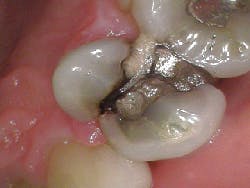

A healthy 55-year-old male presented with the chief complaint that his gum tissue on the upper right side had been hurting for the last few months. He thought something was stuck in the tissue and had unsuccessfully “tried to pick out whatever was stuck in there.” He pointed to the area around tooth No. 3.

A radiograph assessment revealed a slight radiolucency at the apex of the palatal root on tooth No. 3 (figure 8). Biting and percussion was WNL; probing depths were 6 mm interproximal and 3–4 mm on the facial/lingual. Cold and electric pulp tests were negative. The vestibular area in the No. 3–4 area was tender to palpation. Clinically, a large fracture line was noted on the lingual and on the distal marginal ridge (figure 9).

Diagnosis: Necrotic No. 3 with likely association of extended fracture line into the pulpal space. Recommendations were given to the patient, who opted for extraction and eventual implant placement. Upon removal of the tooth, the following was noted (figure 10):

- Lingual fracture line extending approximately 5 mm below the CEJ

- Existing restoration was removed and the crack line was observed to run across the pulpal floor in a mesiodistal fashion

- Wedging was done, and there was a noted flexuration in the cusps